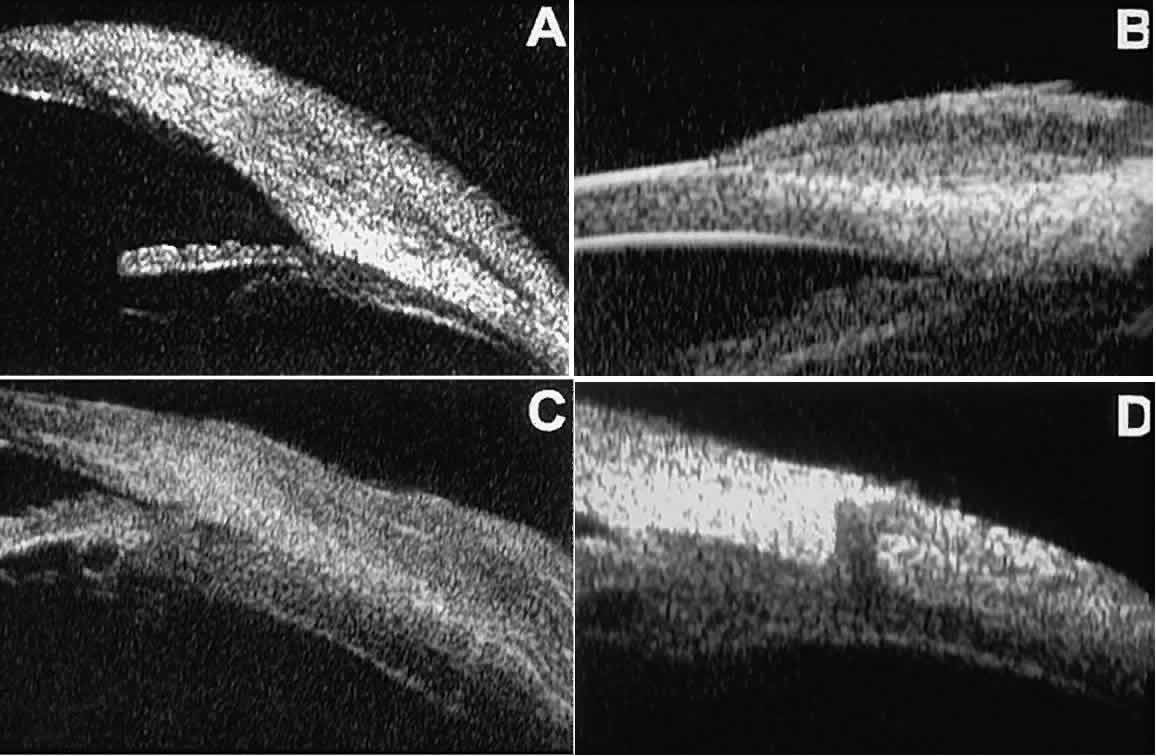

Ultrasound biomicroscopy has also been used to evaluate several anterior scleral disorders,11 including nodular anterior scleritis and scleral hyaline plaques (Fig. 16). On UBM, nodular anterior scleritis (see Fig. 16A) appears as a localized thickening and altered reflectivity of the inflamed sclera. In diffuse non-necrotizing anterior scleritis (see Fig. 16B), UBM shows generalized pronounced thickening of the sclera in the region of involvement. In contrast, after a bout of necrotizing anterior scleritis, UBM can show thinning of the damaged sclera (see Fig. 16C). In eyes with one or more scleral hyaline plaques (see Fig. 16D), UBM shows the lesion to be a highly sonoreflective plate located just anterior to the insertion of the medial or lateral rectus muscle; the lesion has well-defined margins and is so sonoreflective that it shadows the underlying layers of the eye wall.

Fig. 16. UBM features of anterior scleral disorders. A. Nodular anterior scleritis appears as fusiform thickening of limbal sclera. Note apparent lamellae of heterogeneous reflectivity within region of thickening. B. Diffuse anterior scleritis appears as nonfocal scleral thickening in region of inflammation. C. Scleral thinning subsequent to necrotizing anterior scleritis. Note underlying vitreous cells. D. Scleral hyaline plaque appears as dense, hyper-reflective plate several millimeters from horizontal limbus; dense lesion “shadows” deeper tissues.